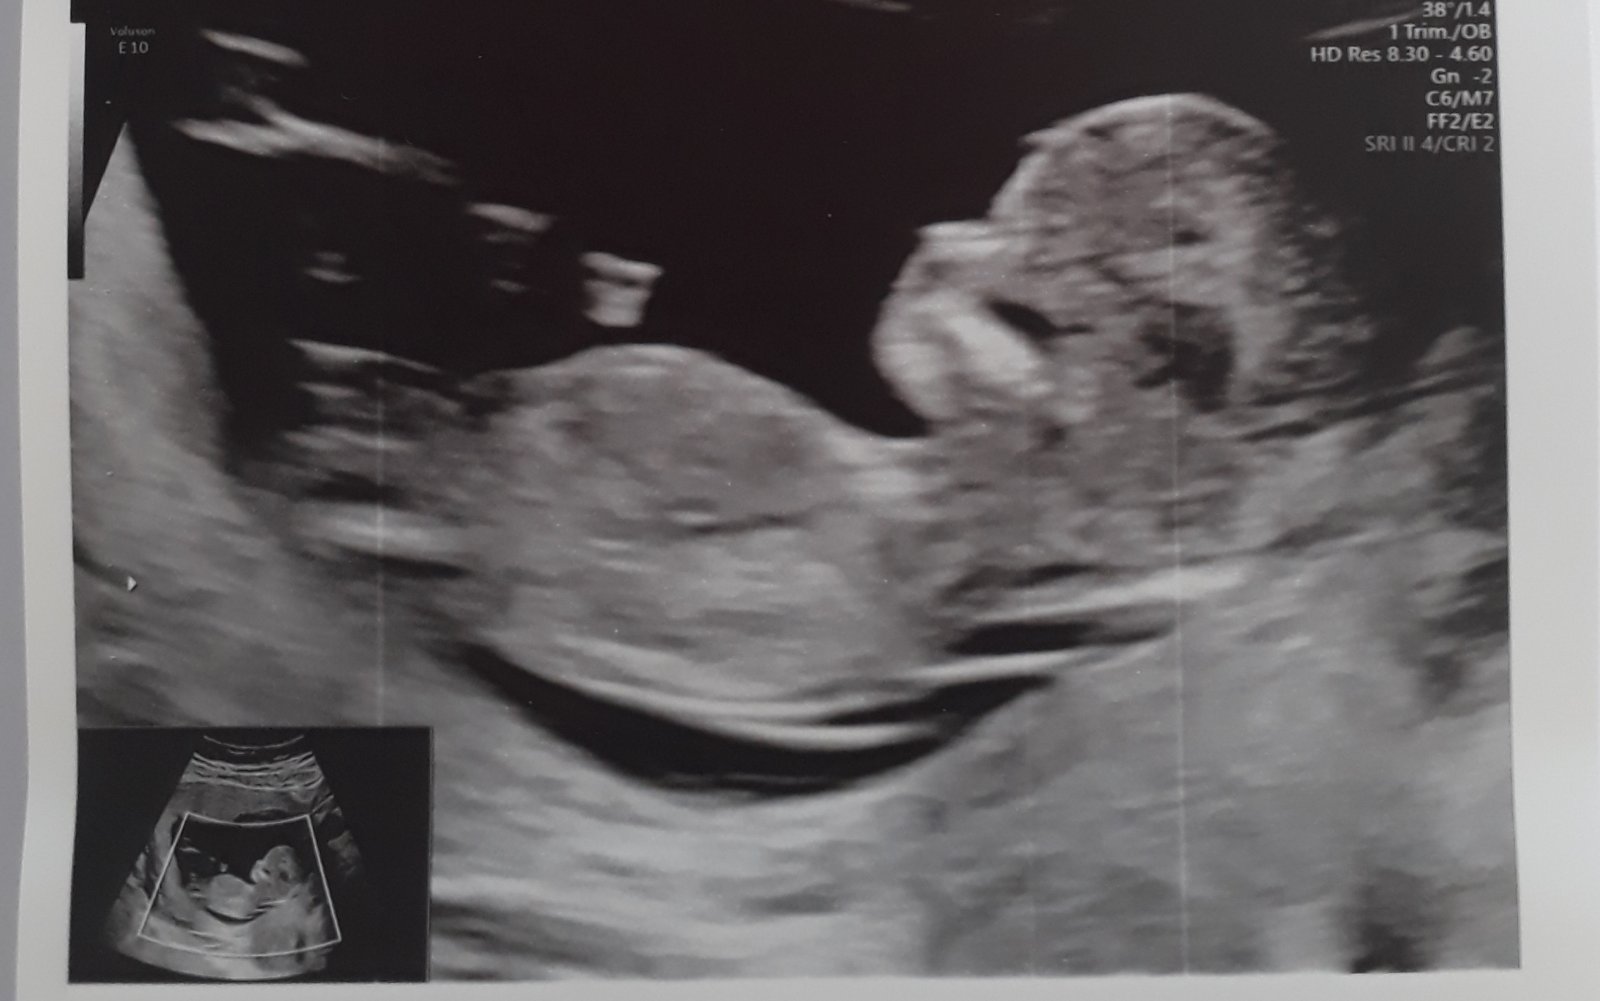

@ivca_ch proč myslíš? Ten UZ se má dělat mezi 12. a 14.tt, to jdeš úplně uprostřed toho rozmezí.😉 mně takto v nemocnici objednali a byla jsem překvapená kolik toho bylo vidět (pan doktor tam prohlížel mozkové hemisféry, oční čočky, srdíčko..)